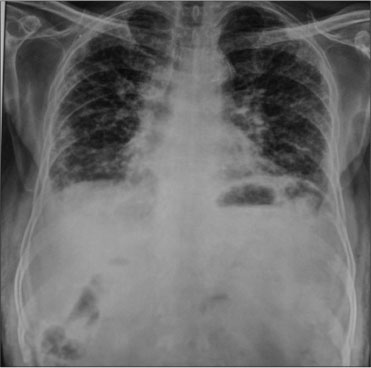

CT scans of the chest and radiograph of the chest [Figures 1], [2], [3] showed inter- and intralobular septal thickenings in the bilateral lung parenchyma predominantly in the lower lobes with peribronchial and fissural nodularity, suggestive of either sarcoidosis or ILD. The patient had a history of chronic cough till few months back which was self-limiting. There was no history of breathlessness, and he was moderately physically active before the present episode. His serum calcium and angiotensin-converting enzyme levels were normal, thus excluding sarcoidosis.

| Figure 1 Pretreatment computed tomography scan chest, coronal view